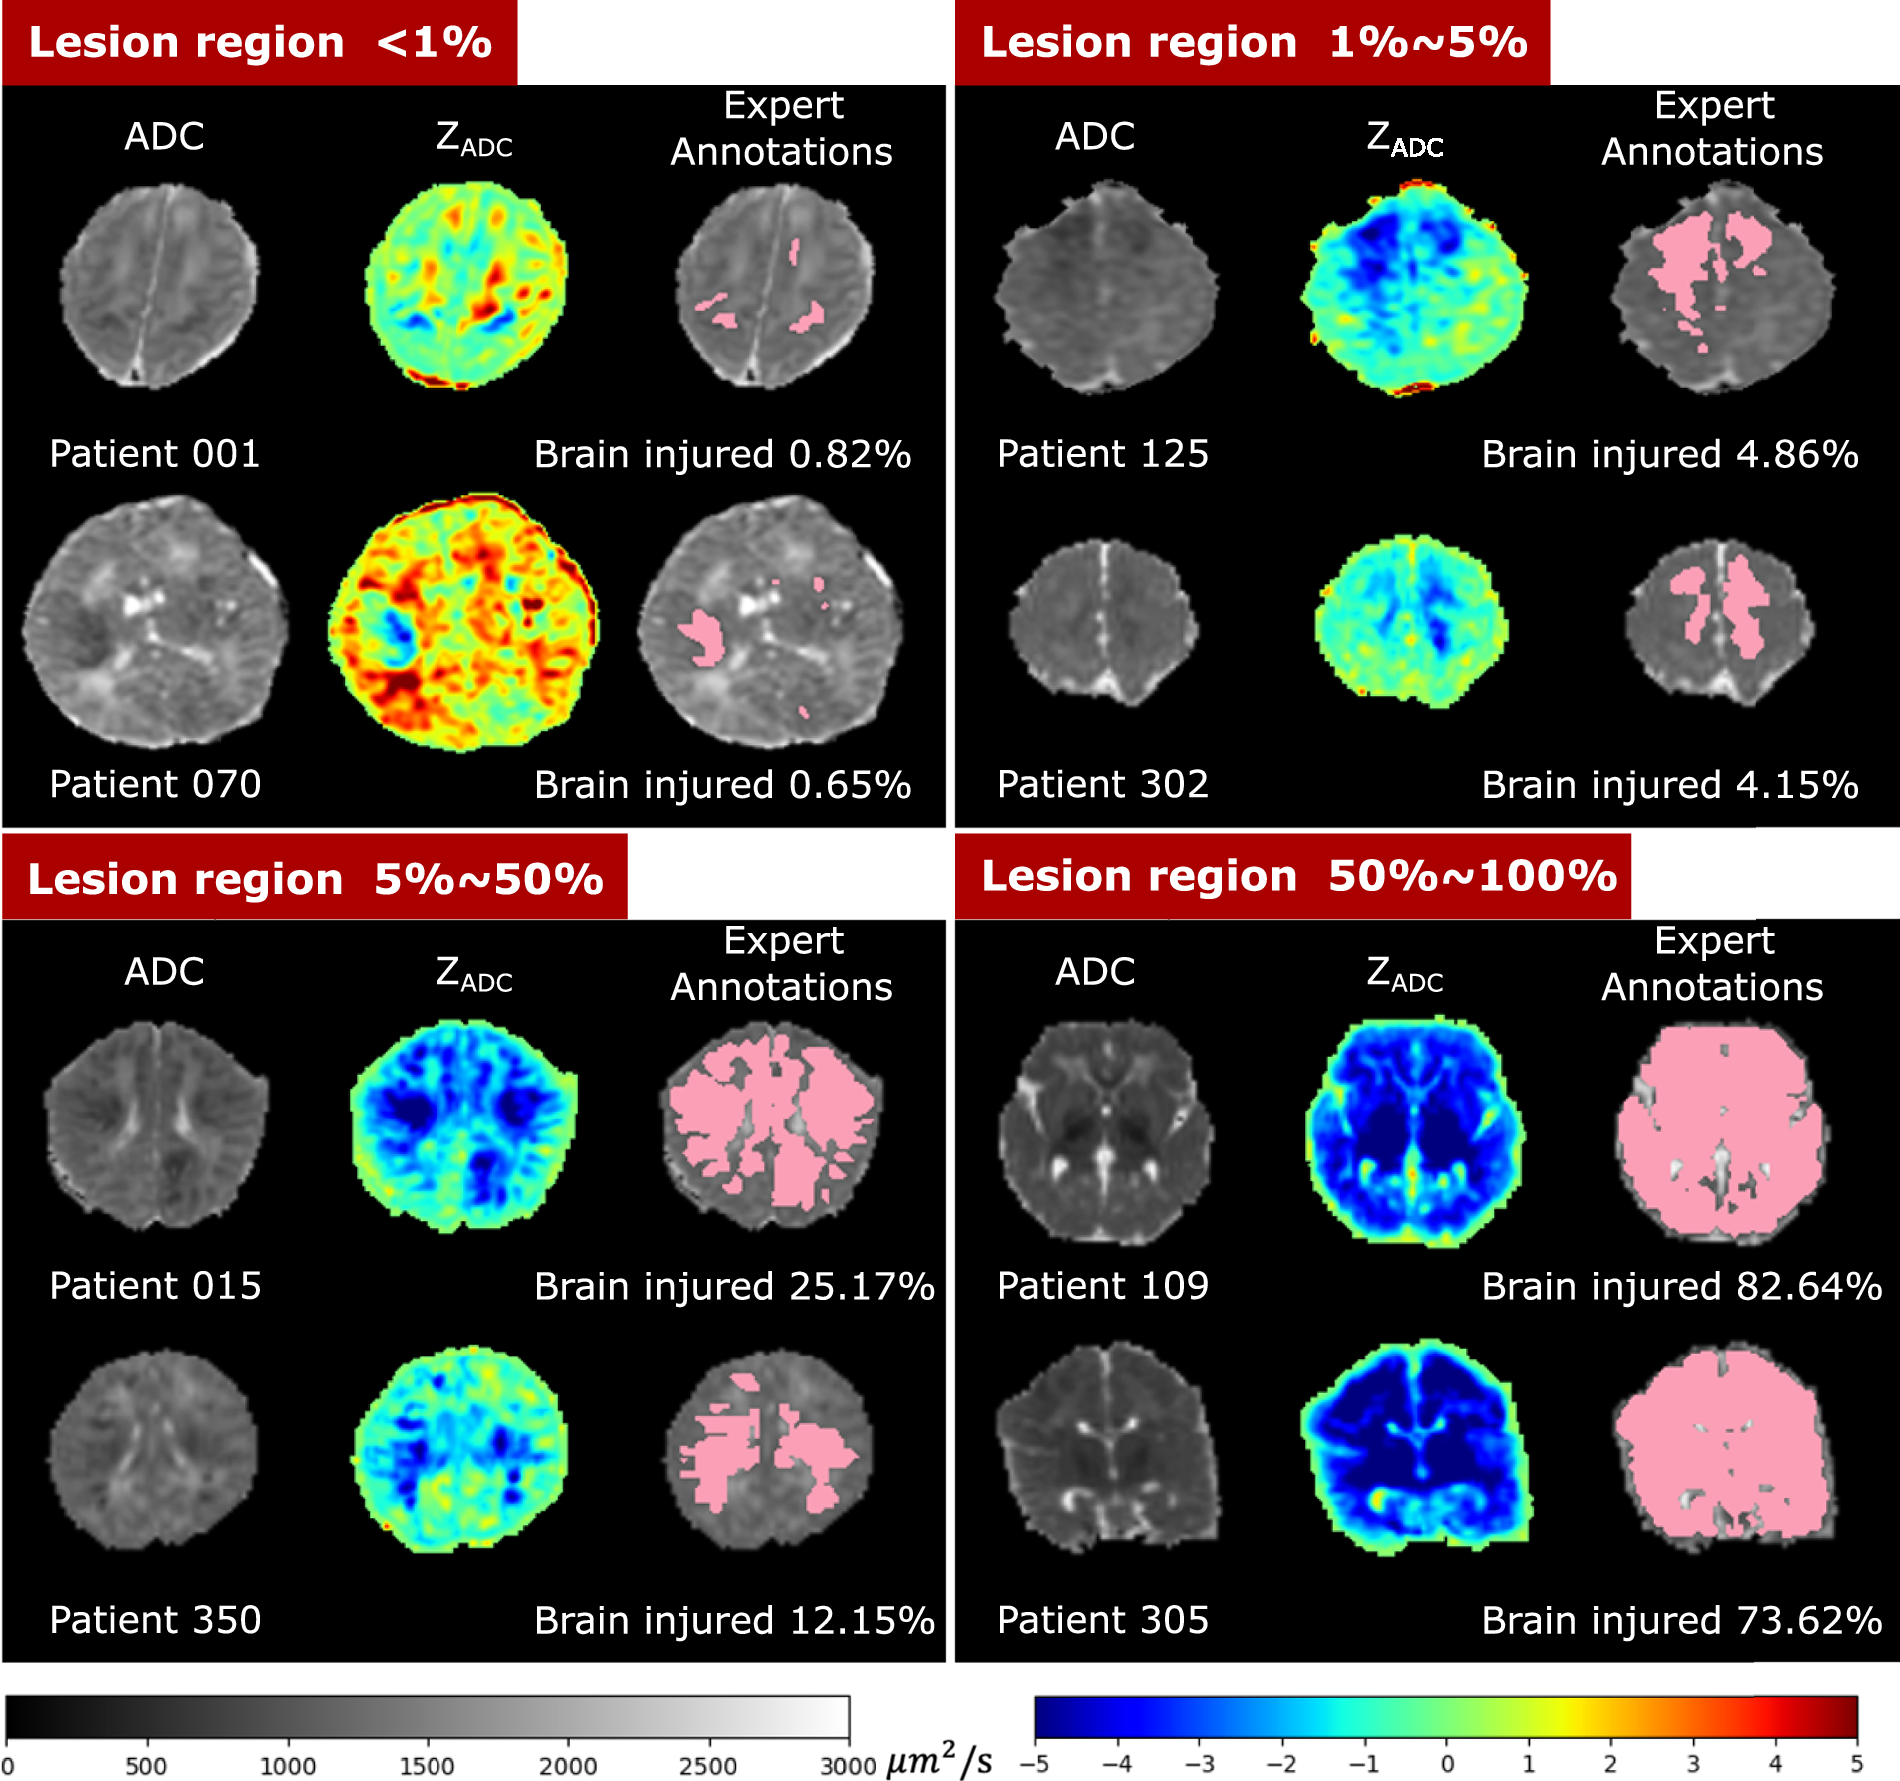

Fig. 5

Visualization of patients with different lesion percentages. In every patient, the left image is the ADC map (skull stripped) with range of ADC values designated by the gray scale bar, the middle is the computed ZADC map with range of Z-scores designated by the rainbow scale bar, and the right image is the expert-annotated lesion regions (pink) overlaid on the ADC map. Percentages of injury were calculated by the volume of the expert-annotated lesion regions divided by algorithm-extracted whole brain volumes (including ventricles).